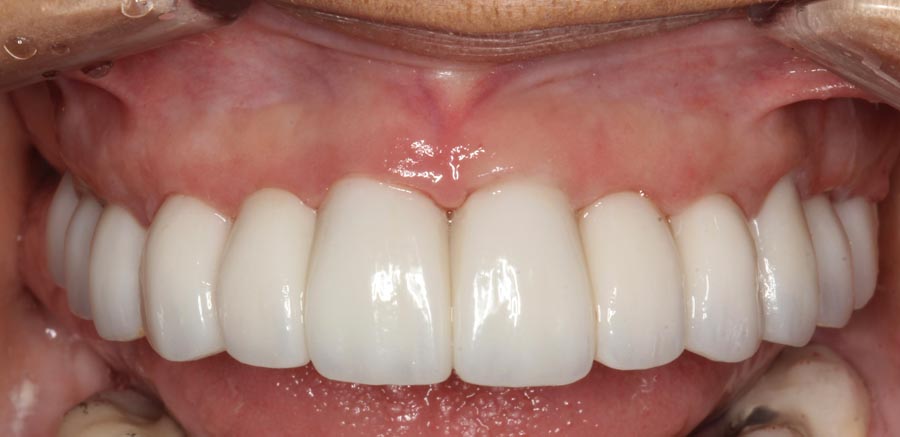

Smile GalleryImplant RestorationsFull Mouth Implant Restoration Full arch zirconia implant bridge (full smile) 1 of 37 Pre-op full smile Pre-op lips retracted Pre-op panoramic x-ray Extraction of strategic teeth Placement of implants Extraction of some remaining teeth after verification of adequate implant stability Occlusal view Post-op panoramic x-ray Immediately fabricated provisional restoration (tissue side view) Immediately fabricated provisional restoration (occlusal side view) Immediate provisional delivered on day of surgery Immediate provisional 2 weeks later Scalloped tissue developed from the provisional at 2 weeks Jig used for making a master impression Provisional in place (full smile) Provisional in place (lips retracted) Provisional in place (right side) Provisional in place (left side) Wax try-in (full smile) Wax try-in (right side full smile) Wax try-in (left side full smile) Wax try-in (full face, lips together) Wax try-in (full smile) Wax try-in (right side) Wax try-in (left side) Wax try-in (lips retracted) Full arch zirconia implant bridge on master cast (frontal view) Full arch zirconia implant bridge on master cast (occlusal view) Implant positions and soft tissue representation on master cast (occlusal view) Soft tissue representation on master cast (frontal view) Full arch zirconia implant bridge (tissue side view) Soft tissues on day of delivery (occlusal view) Soft tissues on day of delivery (frontal view) Full arch zirconia implant bridge delivered (lips retracted) Full arch zirconia implant bridge (lips retracted, close up) Post treatment panoramic x-ray Full arch zirconia implant bridge (full smile)